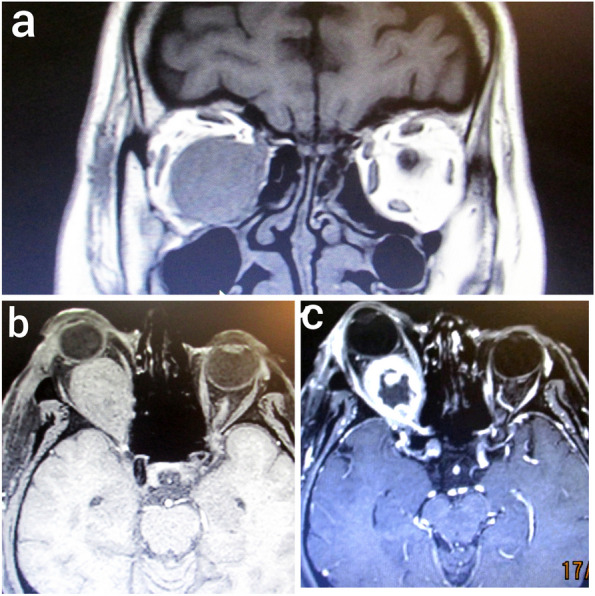

Result: A 55-year-old female, who presented with right-sided exophthalmos persisting for seven months and a week-long history of decreased visual acuity. Orbital computed tomography (CT) revealed a solid, isolated, well-circumscribed mass confined to the right intra-conal orbital cavity. Surgical excision via lateral orbitotomy confirmed the diagnosis of metastatic PTC.

Conclusion: Most cases reported in the literature have identified orbital masses concurrently with the initial diagnosis of thyroid carcinoma. In contrast, our patient exhibited ocular symptoms following a prolonged interval after normal post ablative iodine imaging, highlighting a significant delay in metastatic presentation. Moreover, the solid and well-defined nature of the metastatic orbital mass, confined solely to the orbital cavity without evidence of bony destruction, muscle involvement or intracranial extension in this patient, constitutes a distinctive clinical feature rarely documented in existing case reports.